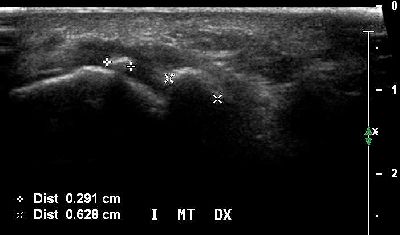

Ipoplasia dei sesamoidi del primo dito (img. 02) Ipoplasia dei sesamoidi del primo dito (img. 02)